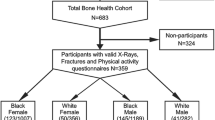

From a database comprising 3,379 left-hand radiographs from the 1ZLS, we selected 3,121 radiographs (1,661 from boys, 1,460 from girls) from 231 healthy Caucasian children (119 boys, 112 girls) by the following exclusion criteria: radiographs from children with bone age < 3.0 years (n = 3) or girls with chronological age > 18.5 years (n = 145) or boys with chronological age > 19.5 years (n = 94) or poor radiograph quality (n = 16). The three radiographs excluded due to bone age < 3.0 years, the only ones left in this bone age-range after removal of decayed film material, were excluded for statistical reasons. Bin sizes up to 6 years’ chronological age were also reduced due to decay of some films. The 239 radiographs from the oldest boys and girls were excluded because in this age range the 1ZLS only covered subjects who were still growing, so these would on average be skeletally delayed. The 16 radiographs excluded for quality reasons were found by screening longitudinal charts for outliers [40]. The children of the 1ZLS were born between January 1954 and February 1956 and were selected randomly within the first 2 weeks after birth [35, 36]. Girls and boys were followed until the age of 18 years and 19 years, respectively, and beyond this until their height gain was less than 0.5 cm per 2 years. Ninety-four percent of the radiographs were taken within 2 weeks of the child’s birthday and 99% within one month thereof. Data were classified by gender and chronological age, bone age or height interval. This gave 33 bins of chronological age-related and 33 bins of bone age-related data (range 3–18 years for girls and 3–19 years for boys in either case). Height-related data were only considered for children in the height-range 100–160 cm, giving 1,978 radiographs split into 24 bins (12 five-cm intervals for both genders). Due to the cut-off age, our bone age-related data are subject to a bias towards early maturers at the upper end, as explained in a study on the development of T, W, M and L in the same population [40]. This would affect bins 18–19 in boys and 17–18 in girls. Data outside the intended bone age-ranges of the software (> 17 years in boys and > 15 years in girls) should not be used for reference purposes anyway. These biased data were included in the study, since they may reveal interesting characteristics of early maturers. This was found to have no influence on the outcome of the present comparison of metacarpal indices. Figure 1 shows the exclusion criteria applied to obtain the final data sets and subsets.